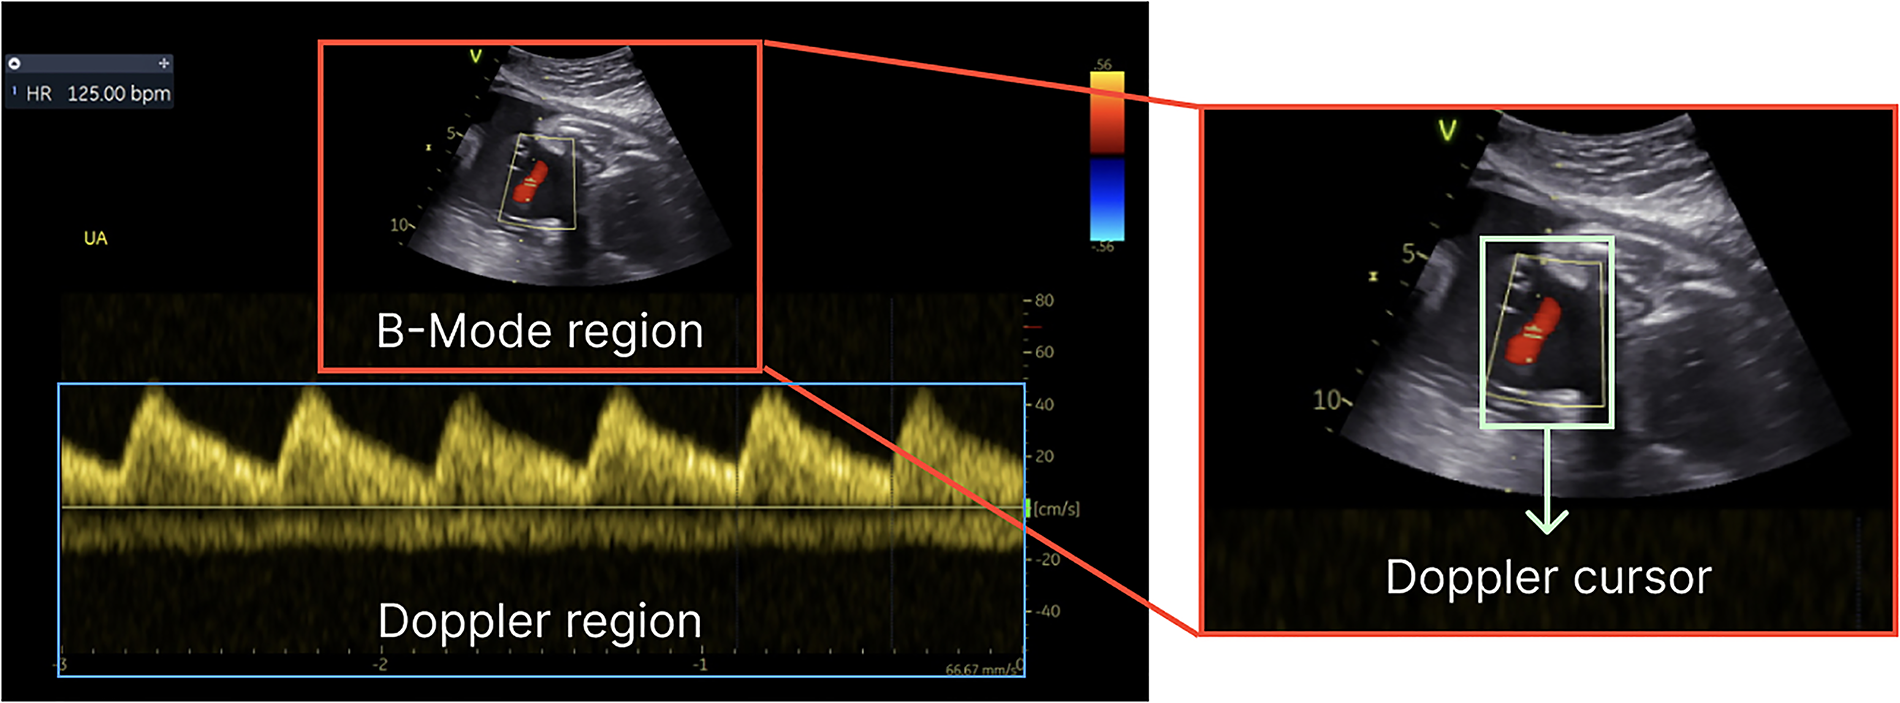

In a standard feto-placental Doppler study, a sequence of Doppler images is acquired over time and manually analyzed to evaluate fetal health. In addition to the Doppler spectrum, which represents the blood flow velocities over time (with the x-axis representing time and the y-axis showing the velocity of the blood flow), the Doppler images also include a brightness mode (B-mode or 2D) subimage. The subimage is employed to identify the specific spatial location from which the Doppler spectrum is obtained, as illustrated in Figure 1. It represents the anatomical structure at the designated time point and serves as a fixed reference point to facilitate visualization of the region where the Doppler measurements are being conducted. The acquisition time for these images is approximately 45–60 min; however, the subsequent manual analysis may span a longer period due to the following factors: (i) the large volume of images acquired, (ii) the unpredictable foetus positioning inside mother's womb, which increases image variability, and (iii) the numerous measurements required to be performed, as suggested by the ISUOG Practice guidelines (7). The analysis process consists of: (i) labelling each acquired image (classification), (ii) delineating its Doppler trace and (iii) retrieving functional Doppler indices crucial for clinical diagnosis (e.g., maximal peak velocity). Besides being a time-consuming task, this analysis heavily relies on operator's skill and often leads to inter- and intra-observational errors (1). For instance, a study published in 2013 by Vilkomerson et al. (8) reported a 25% inter-observer variability when measuring maximal peak velocity in Doppler images.

Figure 1

Components of a Doppler image—B-mode for structural details, the Doppler region for blood flow information and Doppler cursor on top of the B-mode region.